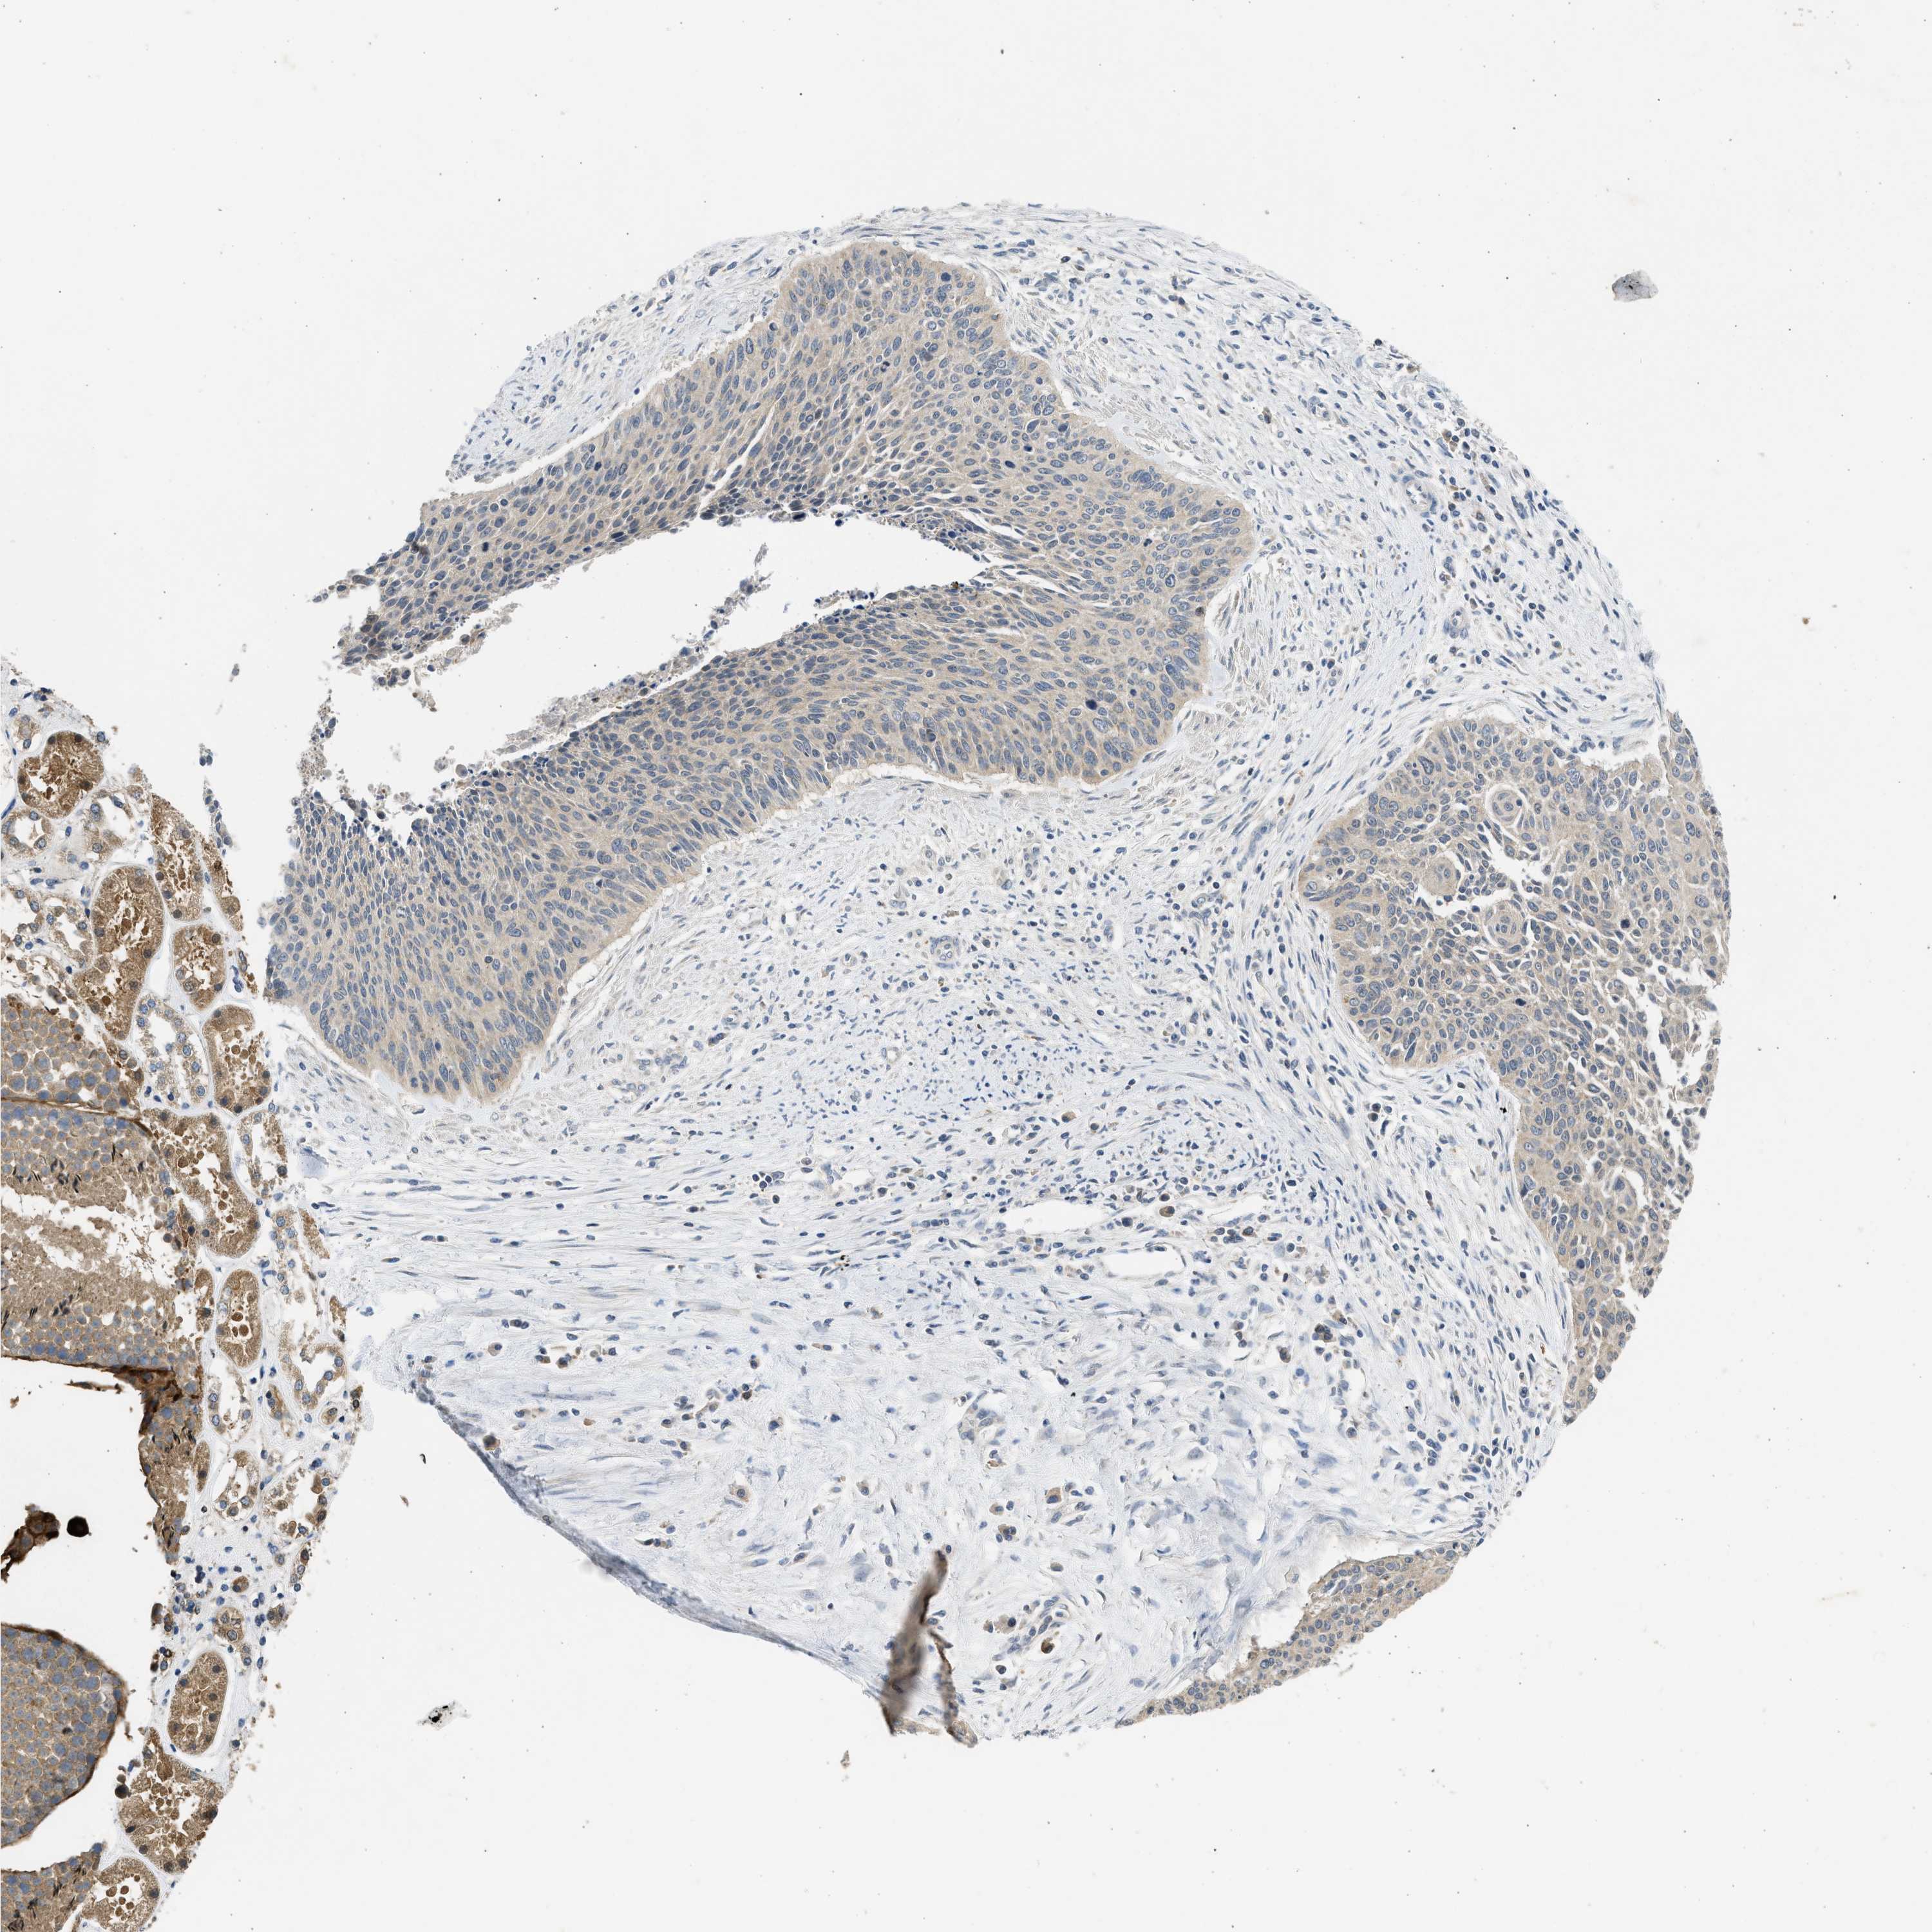

CERVICAL CANCER - Protein expressioni

A mouse-over function shows sample information and annotation data. Click on an image to view it in a full screen mode. Samples can be filtered based on level of antibody staining by selecting one or several of the following categories: high, medium, low and not detected. The assay and annotation is described here.

Note that samples used for immunohistochemistry by the Human Protein Atlas do not correspond to samples in the TCGA dataset.

Antibody stainingi

Antibody staining in the annotated cell types in the current human tissue is reported as not detected, low, medium, or high, based on conventional immunohistochemistry profiling in selected tissues. This score is based on the combination of the staining intensity and fraction of stained cells.

Each image is clickable and will lead to virtual microscopy that enables deeper exploration of all samples and also displays staining intensity scores, fraction scores and subcellular localization as well as patient and tissue information for each sample.

Antibody CAB018654

Squamous cell carcinoma, NOS

Adenocarcinoma, NOS